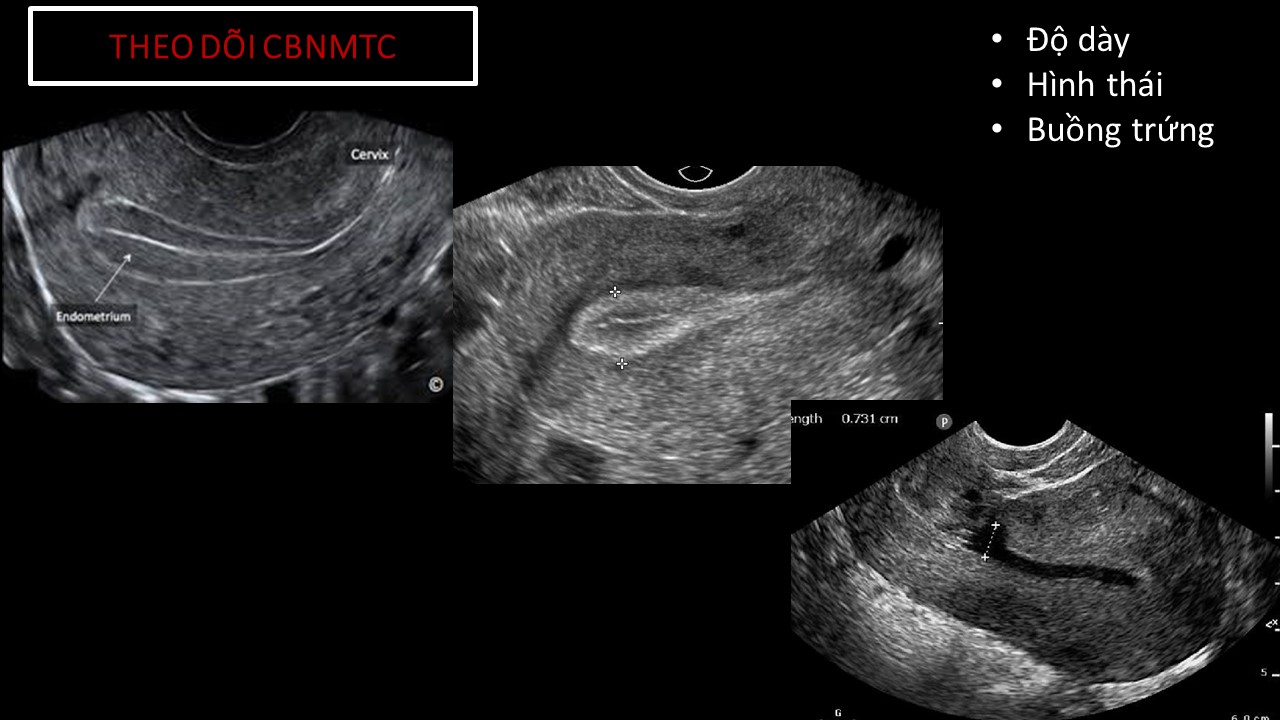

Vai trò của siêu âm trong chẩn đoán và điều trị hiếm muộn